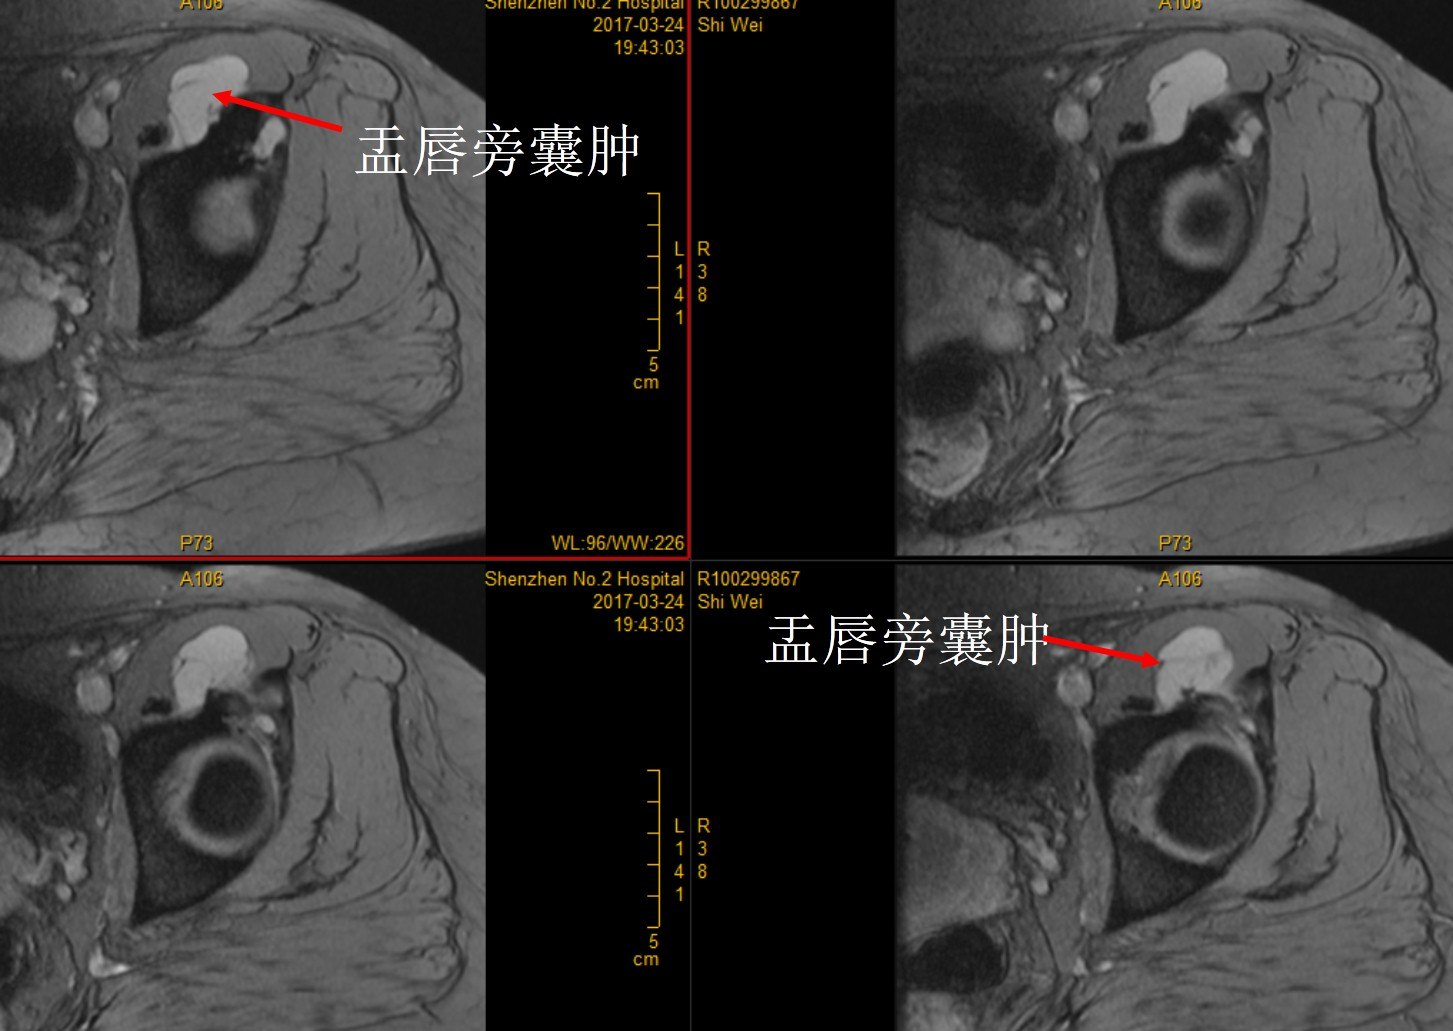

术前检查 X线 CT和单髋MRI

予以髋关节镜盂唇缝合修复+囊肿切除+关节清理术,术后复查MRI提示囊肿切除完全。

X线、CT检查能排除髋关节退变、发育不良、骨关节炎、髋关节撞击等骨性异常结构,但不能很好显示软组织病变,因此不能诊断髋臼盂唇损伤。MR检查具有较好的软组织对比性,分辨率较高,可多方位和多序列的成像,可以直接显示髋臼盂唇的形态和信号。MR检查又有MRI(MR Imaging)和MRA(MR Arthrography)之分,后者又可分为直接关节造影(Direct MR Arthrography )和间接关节造影(Idirect MR Arthrography)。